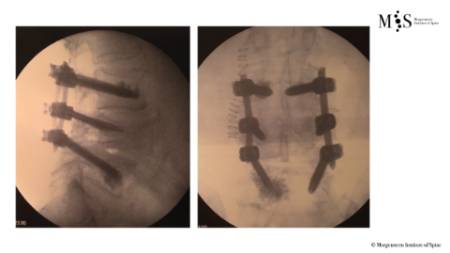

Percutaneous stabilization of unstable vertebral fractures

In cases of complex (unstable, burst, etc.) vertebral fractures, additional stabilization of the fracture by percutaneous stabilization is usually required. In cases where there also is a neurological deficit (muscle weakness, tingling in legs or arms, etc.), a decompression of the spinal canal is additionally required. A percutaneous stabilization of the spine with screws and rods discharges the load on the unstable fracture, stabilizing the whole spine and relieving pain. Depending on the patient’s bone quality, the stabilized vertebrae may be additionally cemented by kyphoplasty.